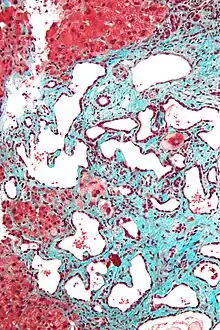

Micrograph of a bile duct hamartoma. Trichrome stain, high magnification